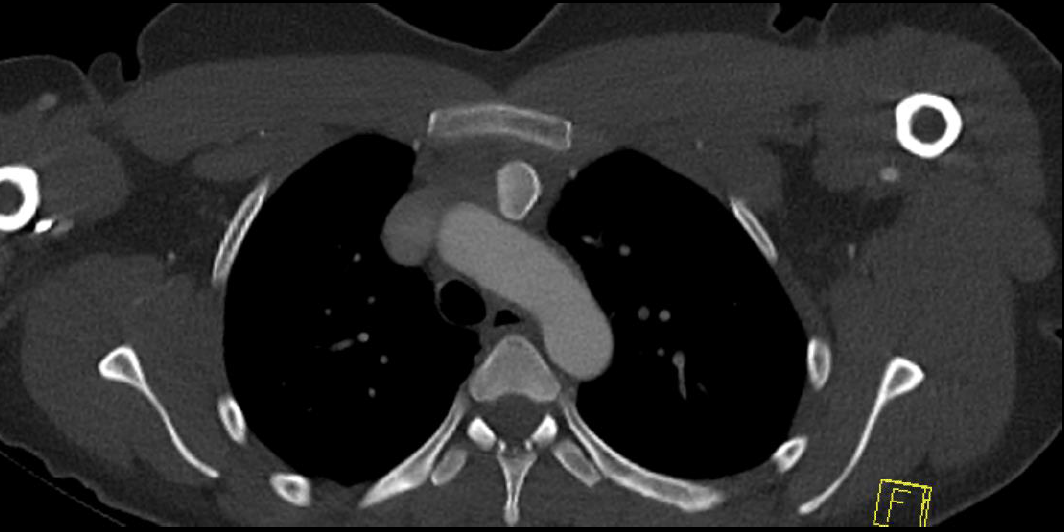

Left posterior SCJ dislocation with pre- and post angiogram

Left posterior SCJ dislocation with pre- and post angiogram

Severe left posterior SCJ dislocation with subclavian vein compression